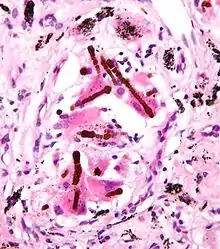

Ferruginous bodies. H&E stain.

A ferruginous body is a histopathologic finding in interstitial lung disease suggestive of significant asbestos exposure (asbestosis). Asbestos exposure is associated with occupations such as shipbuilding, roofing, plumbing, and construction.

They appear as small brown nodules in the septum of the alveolus. Ferruginous bodies are typically indicative of asbestos inhalation (when the presence of asbestos is verified they are called "asbestos bodies"). In this case they are fibers of asbestos coated with an iron-rich material derived from proteins such as ferritin and hemosiderin.[1] Ferruginous bodies are believed to be formed by macrophages that have phagocytosed and attempted to digest the fibers.